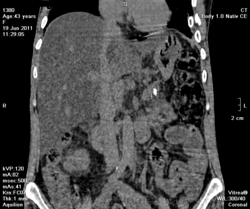

на фоне хр.калькулезного панкреатита опухоль головки поджелудочной железы, распространение на ворота печени, очень подозрительно на инвазию портальной вены и портальную гипертензию. Печень увеличена, гиподенсна, и если не ошибаюсь, цирроз.

Да, цирроз выставил, хотя конечно не такой уж он и показательный, нежели обычно с правильной атрофией и бугристыми контурами. На счет портальной вены тоже засомневался (на нативе прям как одно целое) и рекомендовал контраст, хотя, наверное, тут скорее эгоистический интерес.

Ну еще желчный пузырь и нефроптоз справа (за счет увеличенного вертикального размера печени).

а в желчном камешки, тут я их зажал показать)

и хр. холецистопанкреатит в анамнезе, как мы уточнили - калькулезный;-)

Без контраста только гадать. Может, киста, может, и нет.

По-моему в печени жировой гепатоз. А контрастирование в этом случае обязательно.